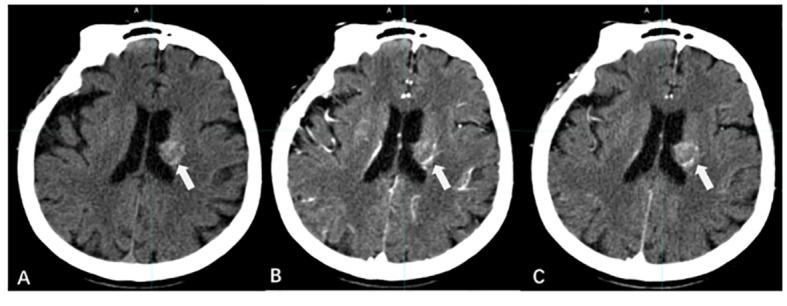

Brain metastases (BMs) are the most prevalent intracranial malignant tumors in adults and are the leading cause of mortality attributed to malignant brain diseases. Radiotherapy (RT) plays a critical role in the treatment of BMs, with local RT techniques such as stereotactic radiosurgery (SRS)/stereotactic body radiotherapy (SBRT) showing remarkable therapeutic effectiveness. The precise determination of gross tumor target volume (GTV) is crucial for ensuring the effectiveness of SRS/SBRT. Multimodal imaging techniques such as CT, MRI, and PET are extensively used for the diagnosis of BMs and GTV determination. With the development of functional imaging and artificial intelligence (AI) technology, there are more innovative ways to determine GTV for BMs, which significantly improve the accuracy and efficiency of the determination. This article provides an overview of the progress in GTV determination for RT in BMs.